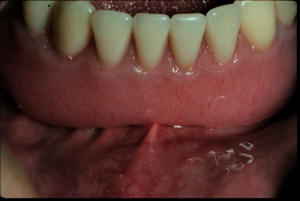

5. Alergias e inflamación

Las alergias al acrílico son muy raras. ver

foto derecha.

Inflamación por falta de higiene de la

prótesis. Ver foto inferior